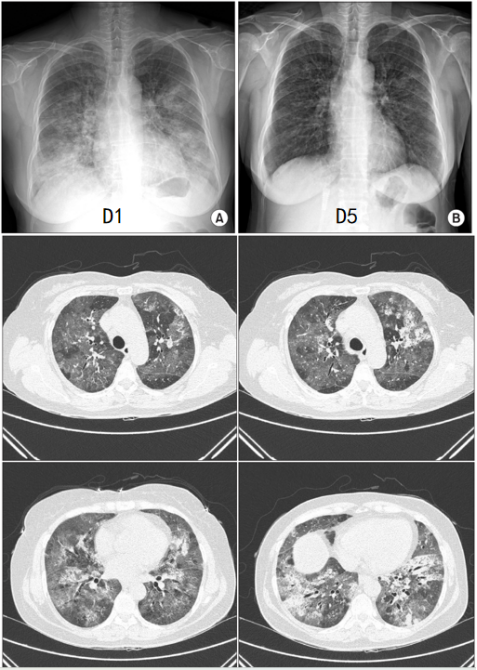

在一例55岁免疫功能正常女性患者中还可以看到两肺弥漫磨玻璃影和小叶中心结节,以小叶间隔增厚为主(图6)。并且该患者在5天内就得到了改善,没有其他病原体。另外一例22岁气急性胸痛5天患者的影像学也是双肺对称的磨玻璃影和实变(图7)

图片

图7  鼻病毒肺炎影像学表现(四)

图源:BMJ Case Rep, 2016, 2016:bcr2015213836.